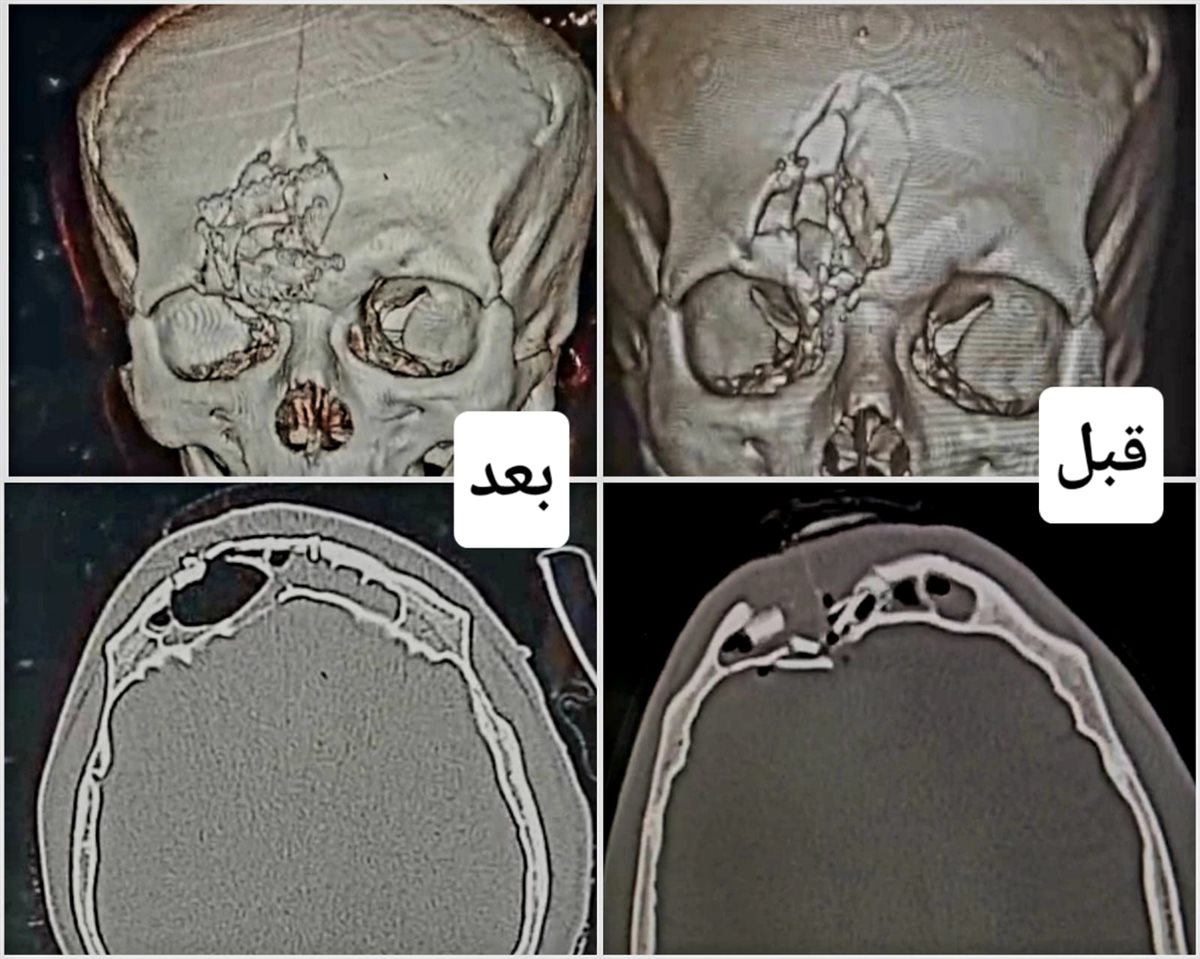

وفي سياق متصل استقبل قسم الطوارئ بمستشفى أجا مريضًا شابًا محولًا من مستشفى السنبلاوين العام، يعاني من تفتيت في عظام الجبهة والجيب الأمامي للمخ، مع كسر في قاع الجمجمة وتهتك في الأم الجافية نتيجة مشاجرة عنيفة. وعلى الفور تم إجراء عملية جراحية تضمنت ترقيع قاع الجمجمة، وإصلاح الأم الجافية، وإعادة بناء عظام الجبهة، وقد تمت بنجاح.